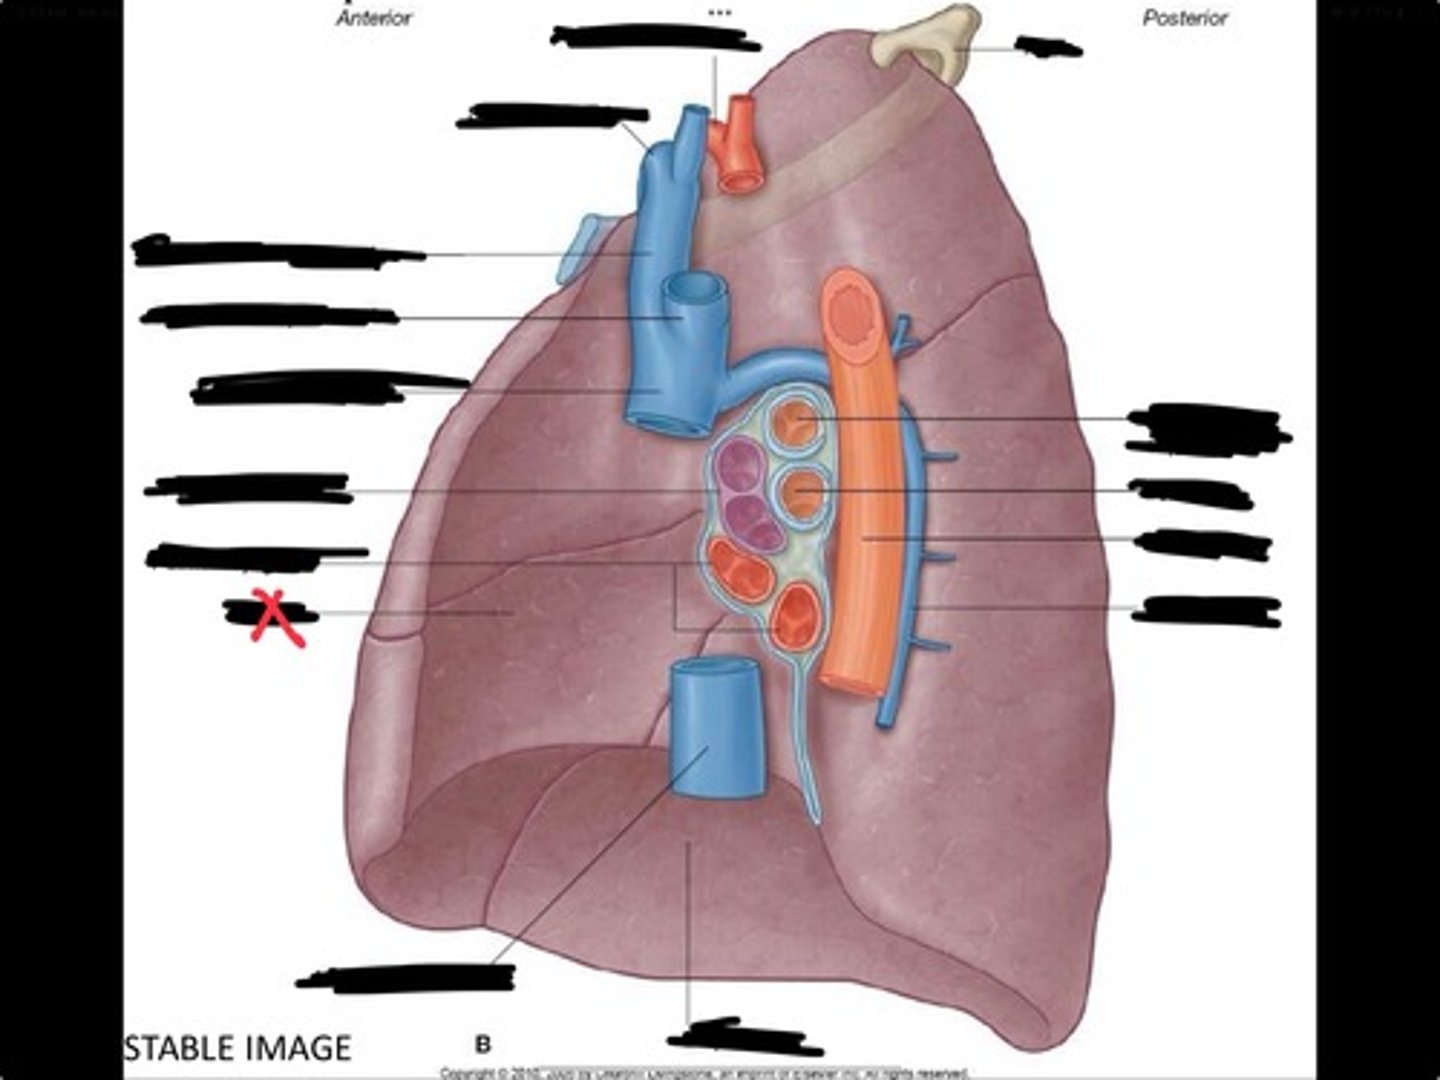

Pulmonary artery

Bronchus to superior lobe

Pulmonary veins